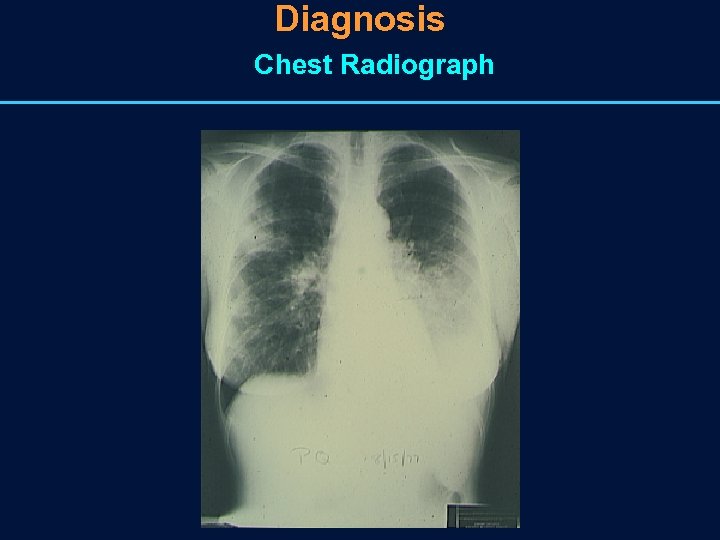

Diagnosis of CAP • Chest radiograph is the most important diagnostic tool • Clinical presentation is not diagnostic of an etiology • Yield of pathogens from Gram stain of expectorated sputum from patients with CAP is only 30%– 40%.

Diagnosis Chest Radiograph